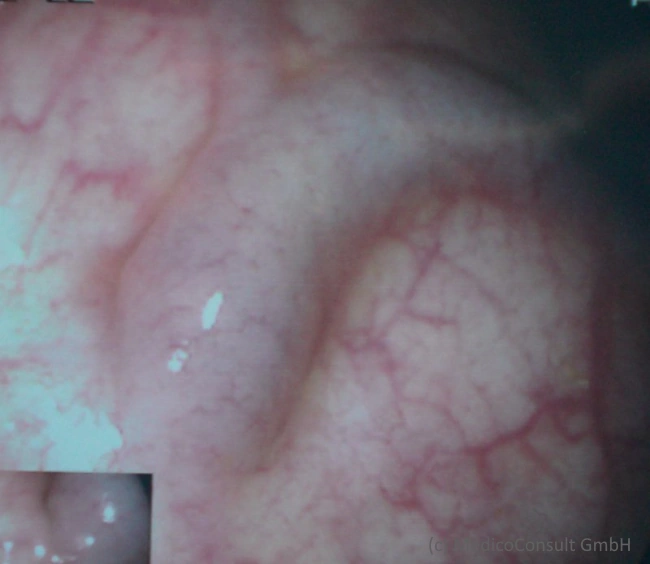

Umgehungskreisläufe (mit Blutungsgefahr: Varizen im Ösophagus und Magenfundus und im Rektum), prominente Venen an der vorderen Bauchwand, Caput medusae (sternförmig vom Nabel ausgehende ektatische Venen bei wiedereröffneter Nabelvene, Cruveilhier-Baumgarten-Syndrom, manchmal Stömungsgeräusch hörbar), am Zwerchfell und Retroperitoneum, an Milz, Niere und am Darm.